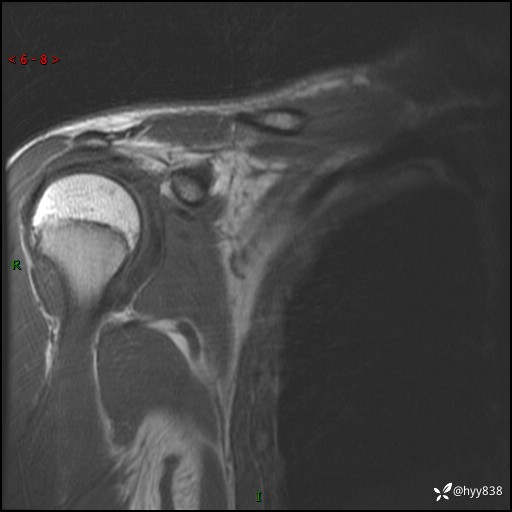

MRI(cor T1WI+T2WIfs+axi T2WIfs)